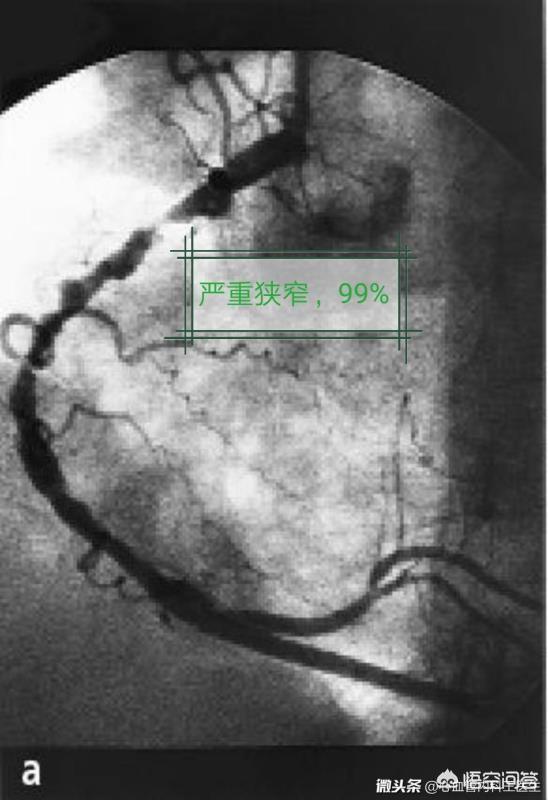

1) Les patients présentant une sténose légère des artères coronaires, une sténose ayant peu d'effet sur la circulation sanguine ou des lésions vasculaires mineures de moindre importance sont généralement traités uniquement avec des médicaments et font l'objet d'un suivi régulier pour observation. Si un stent est implanté à ce moment-là, il risque de faire plus de mal que de bien.

1, stent vide (stent métallique nu) : le stent est un corps étranger au corps humain, qui l'"attaque", provoque une hyperplasie des cellules endothéliales et une réaction inflammatoire, ce qui peut entraîner une re-sténose et une obstruction des vaisseaux sanguins lisses. L'incidence de la resténose et de l'obstruction des endoprothèses vierges atteint 30 %, et ces endoprothèses ne sont plus utilisées.

2、Drug stent : Afin d'éviter une nouvelle obstruction après la pose d'un stent cardiaque, un film de médicament est enduit à la surface du stent métallique, ce qui constitue un stent médicamenteux. Après l'implantation de ce type de stent dans le corps, le médicament est libéré lentement pour inhiber la croissance du tissu cicatriciel autour du stent et maintenir l'artère coronaire ouverte. L'incidence de la resténose et de l'obstruction de l'artère coronaire est ainsi réduite à 10 %.

La resténose au niveau du stent est laL'endoprothèse : Sur une période plus longue (généralement des mois, voire des années), le vaisseau sanguin dans lequel l'endoprothèse a été placée se réobstrue lentement. Ce processus étant très lent, il n'entraîne généralement pas de crise cardiaque et le symptôme le plus courant est l'angine de poitrine.

Selon les données actuelles, l'incidence globale de la resténose du stent à 5 ans est d'environ 10 %.